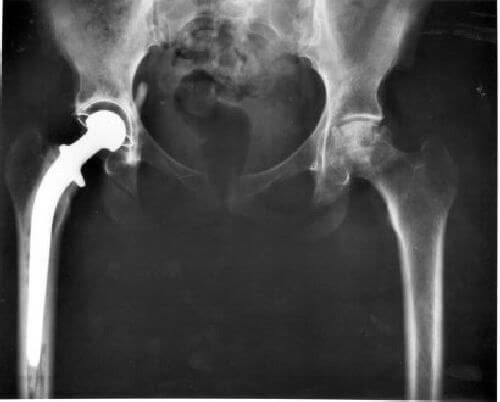

Ten problem ruchowy, jakim jest niesprawność tylnych łap u psów nie zawsze jest spowodowany jedynie starością. Częstą przyczyną tej dolegliwości mogą być na przykład choroby lub wypadki. Istnieją różnego zabiegi mające na celu poprawę stanu zdrowia i mobilności naszego psa. Jednak ich skuteczność jest niestety różna. I co więcej, nie zawsze powtarzalna. Ogólnie rzecz jednak biorąc najlepsze rezultaty zapewniają z reguły zabiegi chirurgiczne.